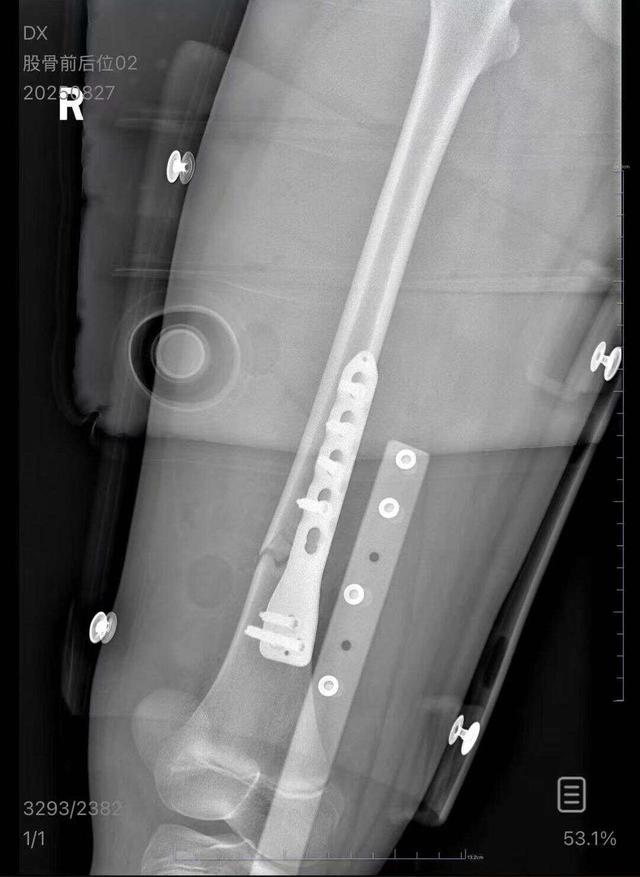

列车上铺乘客跌落砸断下铺10岁孩子腿骨

朱女士向记者出示的医院病历显示,8月24日凌晨,朱女士的女儿到医院就诊。医院诊断朱女士的女儿右股骨骨折,需要住院进一步治疗。

朱女士出示的报警回执显示,8月24日凌晨2点22分,上海铁路公安处无锡站派出所接到报案。报案人称,在某列车上,快要到无锡站时,上铺的乘客下床时没抓稳,导致孩子大腿骨折。